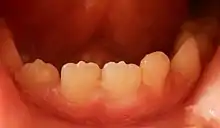

Mamelons on the lower central and lateral right incisors of a seven-year-old boy

A mamelon (from French mamelon, "nipple") is one of three rounded protuberances which are present on the cutting edge of an incisor tooth when it first erupts through the gum. Mamelons' appearance can be smoothed by a dentist if they have not been worn down naturally by biting and eating foods.[1] Mamelons are present on permanent central and lateral incisors. Mamelons are easiest to observe on the maxillary central incisors, and appear as three small prominences on the incisal edge of the tooth. Mamelons are ordinarily of no clinical importance. Usually they are worn off early in the life of the tooth.